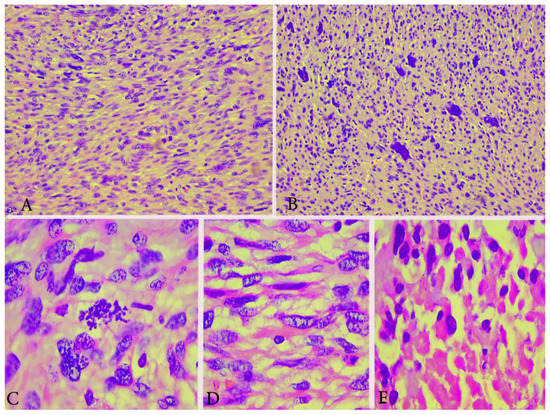

2.1.4. Pathology

Pathology

3.1.3. Pathology